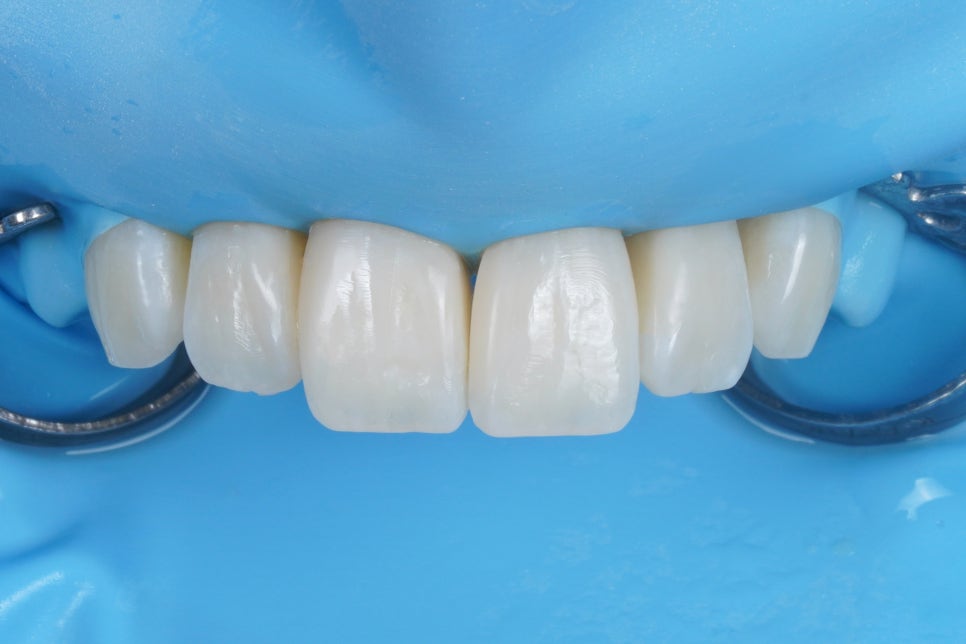

러버댐, 고급 재료인 ISO-DAM을 활용해

구강내 습한 환경과 치아를 격리시켜 줍니다.

이러한 방습/격리 테크닉은

레진 치료에 있어 굉장히 중요합니다.

스카치테이프를 물 묻은 손으로 만지면

손에 붙지 않게 쭈우욱 미끄러지거든요?

그만큼 '접착'에 있어 '수분'은 쥐약입니다.

당연히 아까 치석 얘기 했듯이,

치아 표면에 묻은 단백질 코팅 피막같은 것도

접착에 방해가 되겠죠.

그래서 저희는 에어플로우 GBT 파우더스케일링

장비를 이용해서

치아를 깨끗하게 만든 뒤 레진을 접착하고 있습니다.